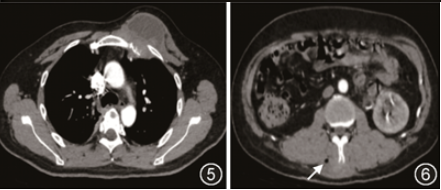

胸部CT(图4, 5, 6):纵隔及右肺门、双侧胸前壁及后腹壁多发囊实性占位性病变,右侧肩胛骨及双侧局部肋骨骨质破坏;头颅CT(图7,8):左顶骨骨质破坏,周围见囊实性软组织肿块,增强扫描后实性成分呈中度强化,囊性成分未见强化。后行超声引导下头部及背部肿物穿刺术,组织病理示(图9):化脓性肉芽肿炎,可见较多多核巨细胞,内可见囊泡状孢子样物,特殊染色结果 PAS(+),六胺银(+);同时将外院右肺下叶切除肺组织送我院病理科会诊,结果示(图10):化脓性肉芽肿性炎,可见大量多核巨细胞,内可见囊泡状孢子样物,特殊染色结果 PAS(+),六胺银(+),考虑为真菌感染,但穿刺组织培养结果阴性,遂行穿刺组织宏基因组二代测序(metagenomics next generation sequencing,mNGS),结果显示:芽生菌属真菌(Blastomyces_percursus,序列数192 870)。

图4 2024年6月8日入院后胸部CT示左胸壁肿物;图5 2024年6月8日入院后胸部CT示肋骨破坏;图6 2024年6月8日入院后胸部CT示后背皮下肿物